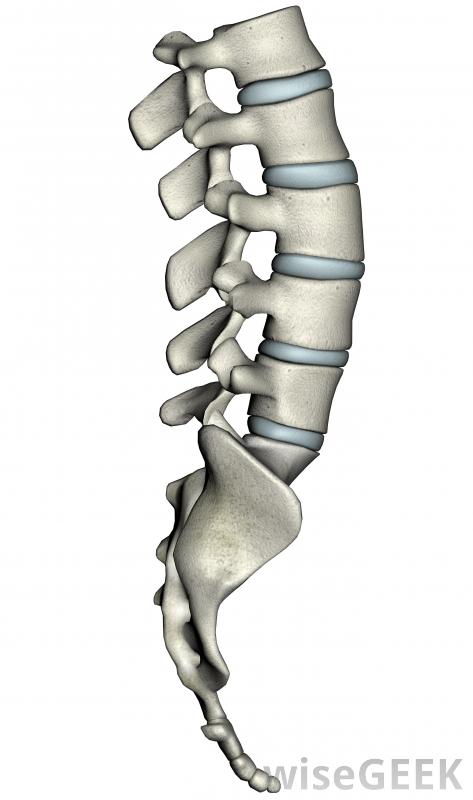

丁香花冠移植可用于脊柱融合手术中稳定脊柱。

从髂骨中获取的骨骼富含生长因子和刺激骨生长的细胞髂嵴移植物可以作为两块骨之间新骨生长的框架。当需要脊柱融合以稳定脊柱时,髂嵴的移植物可以插入两个椎骨之间。这些移植物还可以用于修复腭裂,长骨骨折,无法愈合,骨移植术中的骨缺损是由骨移植造成的髂骨嵴作为自体移植将骨移植回同一患者体内,可消除机体认为移植物是外来物时可能发生的排斥反应。自体骨移植还可减少从其他捐赠者那里感染疾病的机会。